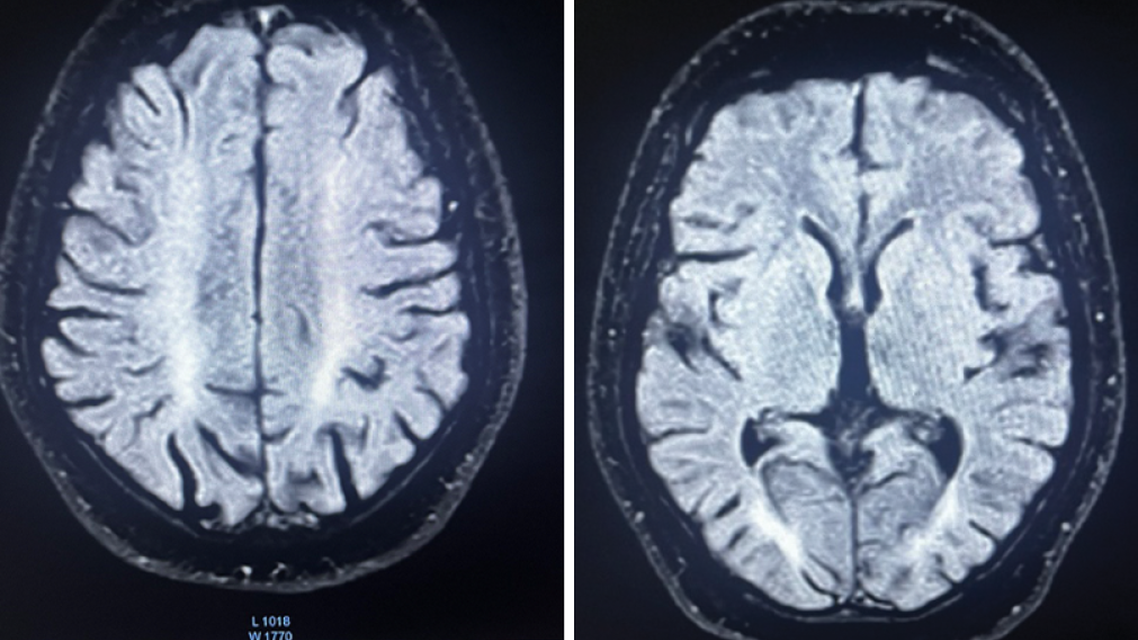

A markedly elevated serum homocysteine level (>44 µmol/L [biologic reference interval, 5–15 µmol/L]) was found. Brain MRI showed symmetric T2 and fluid-attenuated inversion recovery hyperintensities in the bilateral posterior periventricular and frontoparietal white matter, indicative of white matter disease, along with chronic hemorrhagic foci in the bilateral thalami (Figure 2). Magnetic resonance venography confirmed chronic cerebral venous thrombosis. Spinal MRI results were normal. Whole exome sequencing identified an MTHFR sequence variation with autosomal recessive inheritance (c.459C>G), leading to a diagnosis of methylenetetrahydrofolate reductase (MTHFR) deficiency.

Figure 2. Fluid-attenuated inversion recovery MRI of the brain shows periventricular and frontoparietal hyperintensities.